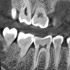

X-ERA SMART verfügt über ein einzigartiges Patientenpositionierungssystem im 3D Bereich, das jede Bildverzerrung durch Patientenbewegung komplett ausschließt. Das Technologiekonzept erzeugt eine Bildqualität in extrem hoher Auflösung. Zwei verschiedene Aufnahmegrößen mit einer Voxel Größe von 80μm / 100 μm liefern in jeder Sichtfeldgröße (FoV) exzellente Ergebnisse für die weitere Diagnostik und Behandlung.

Nacholgend ein paar phänomenale Bilder & Werte,

die nicht nur einem Fachmann die Sprache verschlagen: